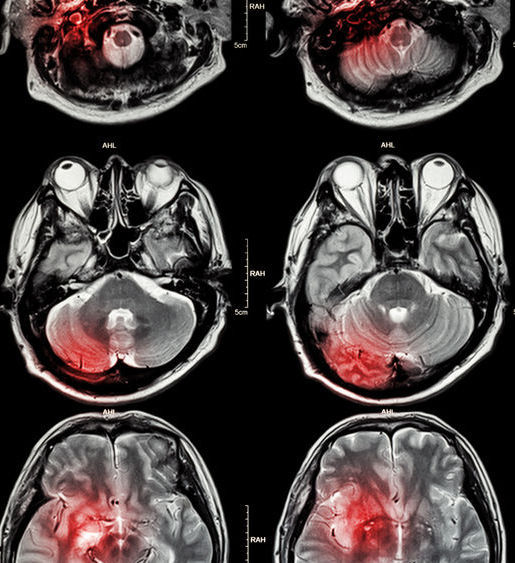

Suna de urgenta la 112. Accidentul vascular cerebral hemoragic. Daca este vorba de un avc ischemic care este cauzat de un cheag sanguin se poate administra un activator tisular de plasminogen t pa un medicament care dizolva cheagurile. Accidentul vascular cerebral se poate produce in timpul somnului iar lipsa severitatii si simptomele minore nu vor interfera cu acesta.

Accidentul vascular cerebral avc se produce atunci cand irigatia sanguina a creierului este intrerupta brusc sau in momentul in care are loc ruperea unui vas cu aparitia unei hemoragii sangele inconjurand celulele nervoase ceea ce conduce la incapacitate functionala. Recunoaşte simptomele şi află cum te poţi feri de un atac cerebral.